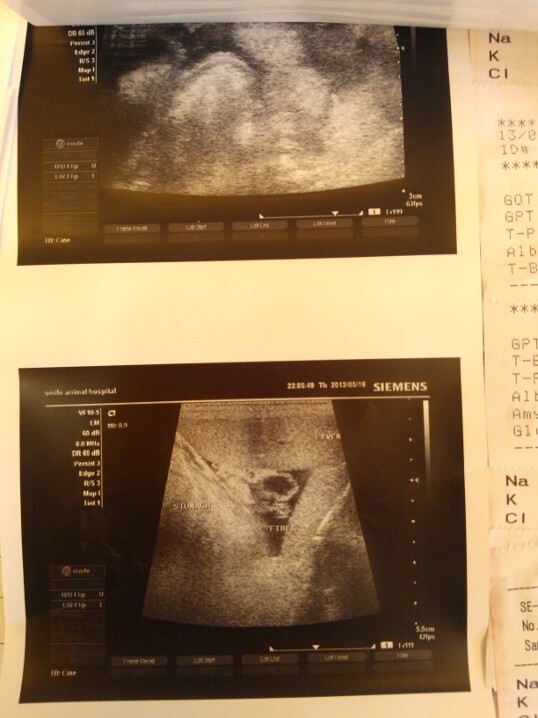

主題: 貧血、黃疸、肝臟腫大的小三花 申請者姓名: 徐慕雯 花色: 申請日期: 2013-06-04 23:44:07 申請者部落格: 申請者臉書網址: 所在縣市/合作醫院: 桃園縣/思邁爾動物醫院 治療費用: 28500元 需求人數: 30人 已結案 (2013-09-03 16:21:48) 報名人員: 牛俊強(已付款)、內湖撲克社(已付款)、王馥玫、chiawei(已付款)、Eligh Liu(已付款)、Weiwen Tu(已付款)、Hanna(已付款)、Winnie Chen(已付款)、小珍 x5(已付款)、Nana Wu(已付款)、catnap(已付款)、Vita(已付款)、yymeow(已付款)、Emily Chou x5(已付款)、treaci(已付款)、你這樣(已付款)、Sammi Yeh(已付款)、Cathy.H(已付款)、Jau Shiang Hsieh(已付款)、鹿皮(已付款)、Tyler Sung(已付款)、呆妹妹(已付款)、小黃、阿珍珍(已付款)、 候補人員: 動物病情說明: 在忠貞市場誘捕的三花貓,原本只是要帶去結紮,沒想到她黃疸、肝臟腫大、嚴重貧血、白血球過高,還有腹水 ~ 狀況非常糟糕 ~

經過輸血及治療,已有稍微穩定 ~

後來轉院做進一步的檢查,發現這孩子是「自體免疫性溶血性貧血」~

是不太常見的疾病,經過住院治療後,小三花已經狀況好轉許多,黃疸指數接近正常,也沒有腹水了,出院後需要居家照顧,至少一個月要服藥及每星期回診血檢 ~